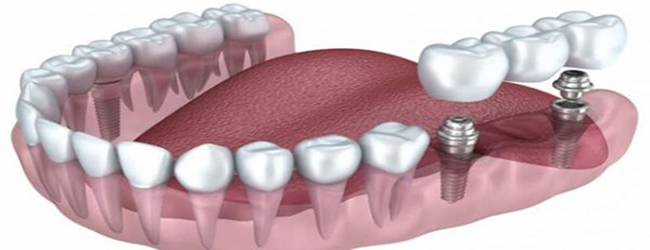

Bunlardan en uygununa karar verildikten sonra çene kemiğine implant yerleştirilir. İmplant tedavisi bir kişinin bir ya da daha fazla dişini kaybettiğinde ve yerine yeni diş yerleştirilmesini istediğinde gerçekleştirilen bir tedavi yöntemidir. Implant diş tedavisi iki aşamadan oluşmaktadır. İmplant tedavisinin süresi yapılacak olan implant sayısına ve hastanın çene kemiğine bağlı olarak yarım saat ile birkaç saat arasında da değişebilir.

İmplant tedavisinin süresi. Bazı markalar daha hızlı iyileşen modeller üretmiştir ve bu süre uygun vakalarda 20 güne kadar inebilmektedir. Konvansiyonel yaklaşımdacerrahisiden sonra alt çenede 8 hafta üst çenede ise 16 hafta kemik ile vidanın kaynaşması için beklenmelidir. Hekim dişe en uygun implantın hangisi olduğuna karar verir.